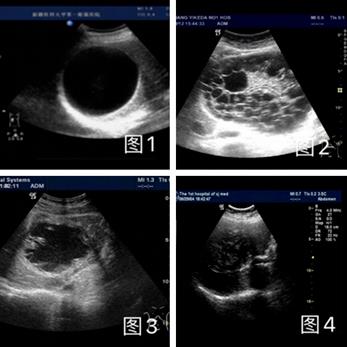

2022.9.5患者至我所门诊部就诊,寄生虫血清免疫学检查:棘球蚴(包虫)IgG阳性。B超检查示:肝右叶囊实性团块,大小约62×55×60 mm。超声显示囊壁增厚呈双层,内囊壁为折叠的膜状回声,呈“水中百合花征”。B超分型:CE-3,内囊塌陷型(见图1)。

图1 B超图像:肝囊型包虫病灶,内囊塌陷状

2、常见的肝囊肿与肝包虫囊肿不同,可通过B超加以鉴别。由于江苏省为非包虫病流行区,超声医生对包虫病诊断普遍缺少经验,而包虫病的超声影像有一定的特征(见图3)。

肝包虫囊肿超声常见的四个类型:

1、单纯囊肿型 2、多子囊型

3、内囊塌陷型 4、坏死实变型